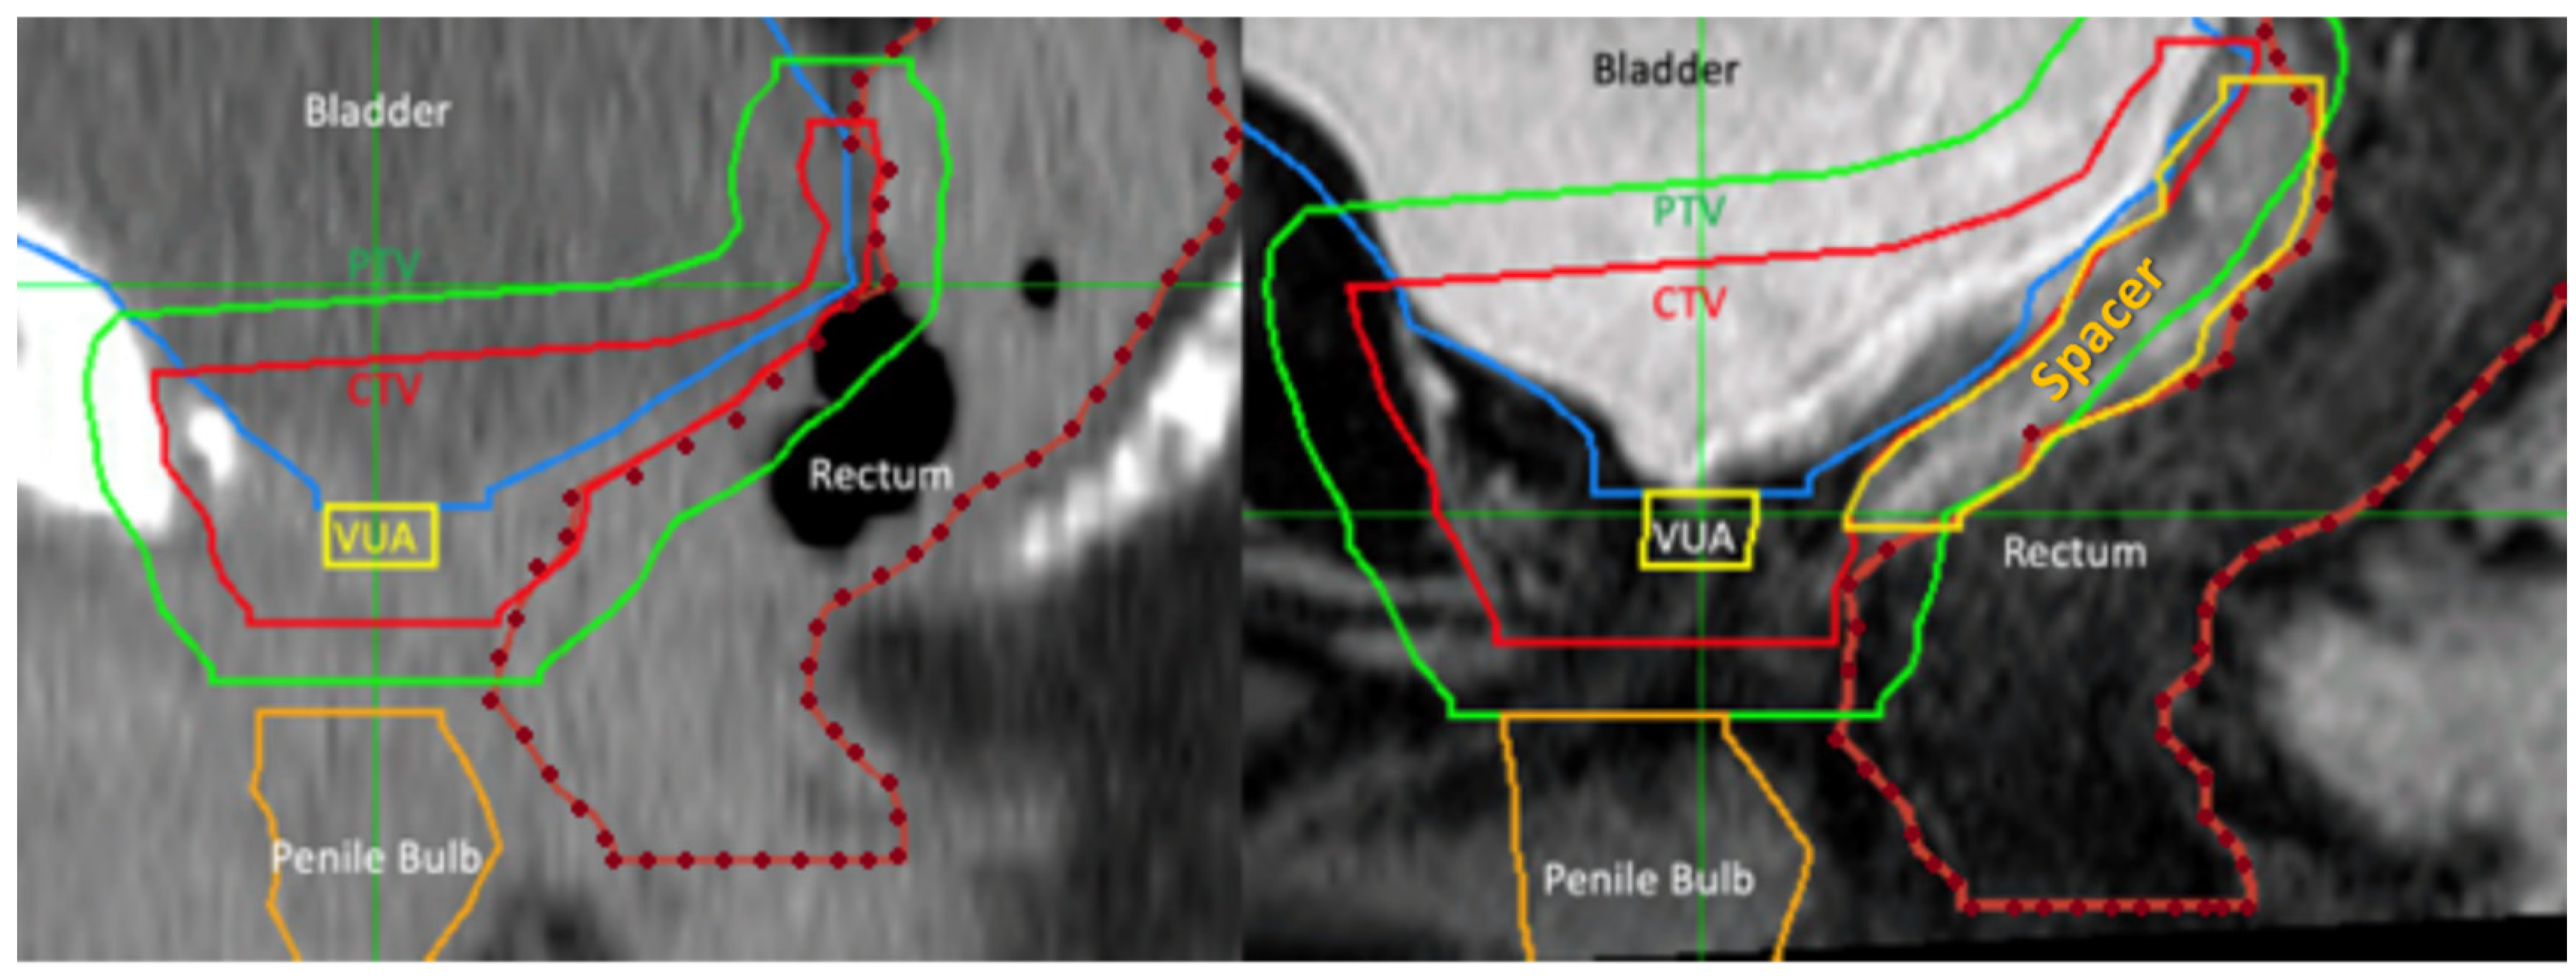

A total of 39 patients had a pre-spacer computerized tomography (CT) scans available for assessment. These are not routine but conducted as planning CT scans prior to a patient-led decision change regarding rectal spacer insertion. Pre- (when available) and post-perirectal spacer CT planning scans, together with post-perirectal spacer MRI scans, were acquired for dosimetric comparison (see Figure 3). The prostate bed CTV was delineated according to standard Australian guidelines [11], and the CTV was uniformly expanded by 7 mm [12] to create the planning target volume (PTV). The prescribed dose to the prostate bed was 70.2 Gy in 1.8 Gy fractions using volumetric arc radiation therapy [12]. Given PSMA-PET scans were negative in these patients, pelvic lymph nodes were not included in the radiation. The PTV and rectal dosimetry for the two sets of CT planning scans (PTV 7 mm/pre spacer and PTV 7 mm/post spacer) were compared.

Figure 3.

Comparison of planned radiation area (green line) in the same patient pre- and post-rectal spacer insertion. Prior to spacer insertion, a long length of rectal wall (delineated by dotted orange line) was exposed to high dose radiation. This decreased by the use of hyaluronic acid spacer (yellow line). Abbreviations: CTV—clinical tumour volume, PTV—planning tumour volume, VUA—vesicoureteric anastomosis.